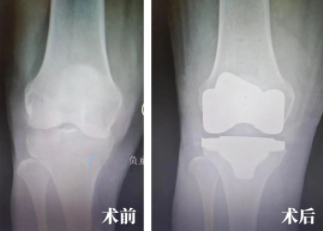

在智能机器人的辅助下,陆奶奶接受了全膝关节置换手术,依靠智能机器人精准定位的特点,手术医生进行了一场用时更短、创伤更小、置换更精确的手术。对于已近八旬的陆奶奶来说,这无疑对术后的康复更为有利!

术中,通过智能机器人可以精准定位到预期规划的位置,完成截骨及假体安装的精准操作,通过这样一套精准化手术流程,可以使患者在术后创伤更小、康复更快、关节功能更佳、假体生存率更长。